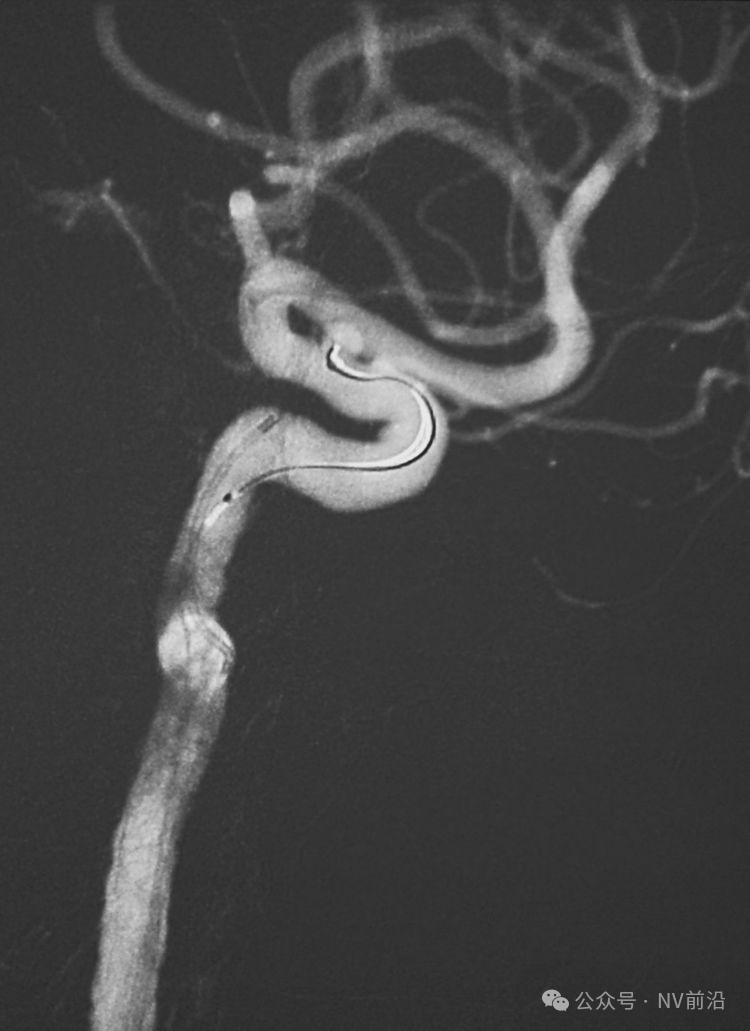

右椎动脉造影三维重建

Echelon 10微导管头无论塑成C形还是S形,均无法稳定于动脉瘤腔内,遂使用回马枪技术,使微导管成襻通过,管头折返入瘤腔。

跨瘤颈释放Solitaire 4×20支架(蓝线),压住微导管(红线),在支架保护下经返折的微导管送入弹簧圈填塞瘤腔。